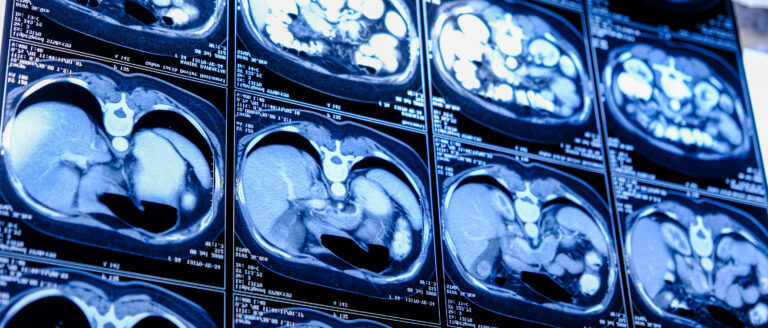

Ist die Hauptschlagader, auch Aorta genannt, erheblich erweitert, liegt ein sogenanntes Aortenaneurysma vor. Droht es zu platzen, kann es für die...